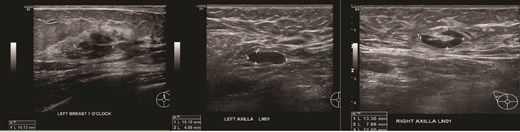

(Left) Ultrasound images of the left breast ill-defined hypoechoic mass; (Middle, Right) Ultrasound images of the axillary lymph nodes with cortical thickening and effacement of the fatty hilum.

(Left) Mammography medioloateral oblique views of bilateral breasts; (Right) Mammography cranial-caudal views of bilateral breasts: Left upper central breast shows a vague focal asymmetry corresponding to the palpable concern, and several prominent right axillary lymph nodes.